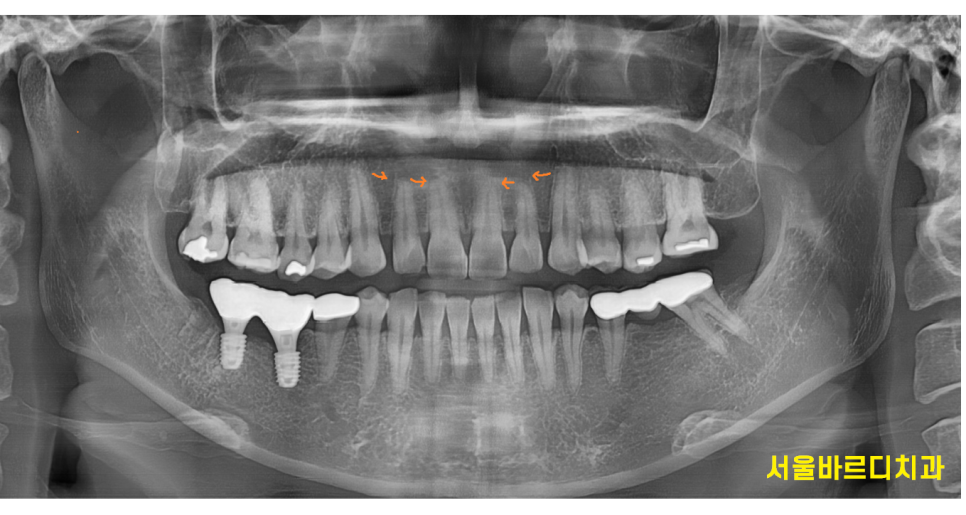

고덕동 교정치과를 찾아오신 40대 여성환자분입니다.

나이가 들수록 치아가 더 벌어지는거 같은데

교합(씹는 부분)은 잘 맞는데

오늘 환자분처럼 앞니 사이 틈이 있어서 보기 싫거나

약간의 삐뚤빼뚤함을 가지고 있을 때 진행합니다.

아래 치아가 없는 부분은 임플란트 치료중이신데

앞니만 교정하기 때문에 임플란트 치료중에도 받으실 수 있습니다!